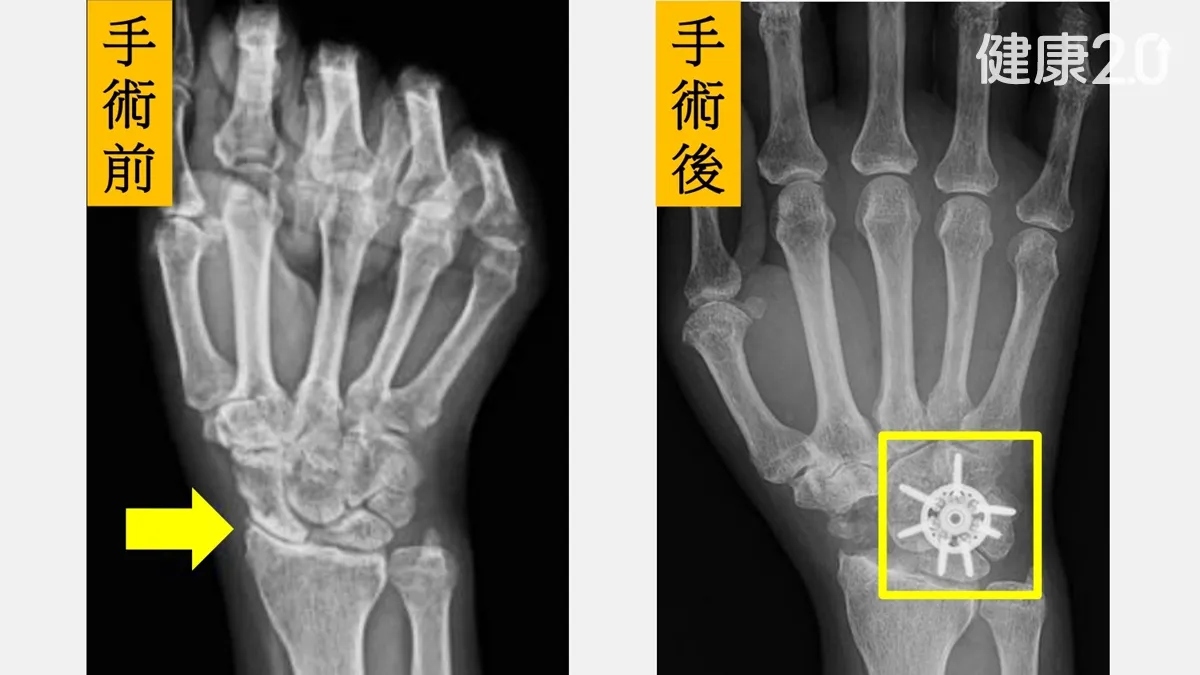

經過醫療團隊的詳細評估,劉先生的X光片顯示病程已屬中後期,最後決定接受「舟狀骨切除合併四角融合術」,這屬於部分腕骨融合術的一種。手術中更使用了新型的「環狀鋼板」來固定。

陳重宇醫師表示,根據最新研究,環狀鋼板能提供比傳統鋼釘、螺釘更優異的初期穩定性,這不僅能提高骨頭癒合的成功率,最大的好處是能讓病人更早開始進行復健,有效降低術後關節僵硬與肌力流失的風險。劉先生術後六周即開始輕度活動,疼痛大幅減輕,現在已能輕鬆拿水杯、轉門把,重拾生活便利。